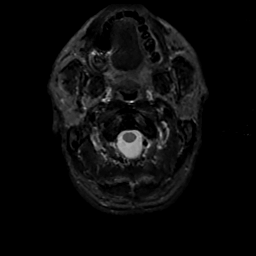

MR Study #13, May 19, 1991 -- Slice #0